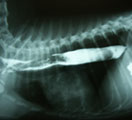

食道造影にて食道拡張が確認された。 内視鏡にて大きな食道内異物を確認した。 バスケット鉗子で部分的摘除。ササミジャーキーだった。 食道内異物完全除去後、やや陳旧性の粘膜裂傷が見つかった。

経過:T:38.8℃、P:120/分、R:60/分。南台動物病院にて食道造影にて食道拡張を認め、異物による食道炎の可能性があると診断されていた。そこで当院にて食道の内視鏡検査を行なった。まず、大きな黄白色の固い異物を確認した。バスケット鉗子で把持したが牽引時に異物の一部が切れてしまった。取り出した異物はササミジャーキーであった。はじめは食道内に残った多量の断片的なジャーキーは内視鏡観察下で大きいものからフィラリア鉗子を用いて一片づつ摘除していた。しかしジャーキー以外の異物はないことを確認したので、小さな断片を噴門前に集めスコープで送気しながら、スコープで胃内に全て押し入れた。食道内異物消失後の精査にて、ジャーキーの角が粘膜に引っかかっていたために生じたと思われる陳旧性の粘膜裂傷を1箇所見つけた。細かい断片処理に時間がかかり処置時間は全部で114分であった。食道粘膜裂傷の影響が心配されたが、次第に食道炎症状は改善し、10日後にはふやかしたフードをよく食べているとのことだった。